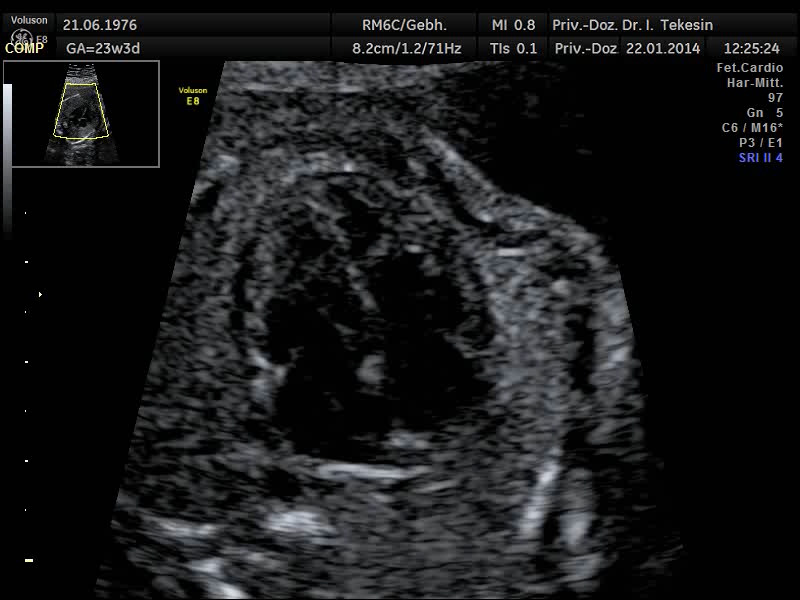

Normaler Vierkammer-­‐Blick

Normaler Vierkammer-Blick